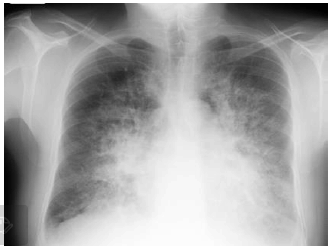

Paciente de 66 anos, do sexo masculino, com antecedente de hipertensão, dá entrada no Pronto Socorro com quadro de dispneia de instalação em horas, após comparecer a churrasco.

Admitido prontamente na UTI, apresenta os seguintes sinais vitais: FC 120, PA 210x120, FR 46, SatO2 90% em máscara de O2. Apresenta, ainda, a seguinte radiografia de tórax:

Enunciado 3137181-1

O paciente foi intubado, iniciada ventilação mecânica invasiva com os seguintes parâmetros em pressão controlada: PEEP 10, PC 15, FR 25, FiO2 100%. Coletada gasometria arterial com o seguinte resultado: pH 7,4, pCO2 40, HCO3 24, pO2 105, SatO2 98%. Tendo em vista os critérios de Berlin para diagnóstico de Síndrome do Desconforto Respiratório do Adulto, esse paciente não se encaixa no seguinte critério: